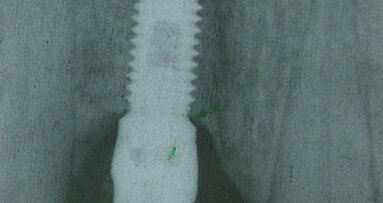

Tra le diverse tecniche a disposizione per migliorare o mantenere un sito osseo implantare, le più diffuse sono l'innesto osseo di apposizione e la ...